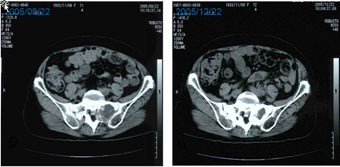

●71歳女性。原発不明がん(転移性骨盤腫瘍)。2005年4月、強い腰痛と歩行障害のため近医を受診。PET、CTにて仙骨左側に径38mm、仙骨右側に径27mmの腫瘤を認め、針生検で腺がんと診断。 ●消化管検査、胸部CT、婦人科的検査でも原発は不明。6月より放射線治療および7月より抗がん剤治療(TJ)が施行されたが、腫瘤はさらに増大、同年9月立ったまま座ることもできない状態となり、主治医に温熱療法をしてほしいと訴えるも同意されず、当センターを受診した。 ●抗がん剤使用は希望されなかった。温熱療法(サーモトロン-RF8)を9月末より2006年5月末まで週1回、計36回。活性化リンパ球を2週に1回、計16回施行した。 ●治療開始2カ月目の11月末には容易に座ることも可能となり、四国(お遍路)に宿泊旅行、階段も上がれるようになった。CEAも9月75.3 ng/mlが12月13.6 ng/mlと低下した。CT上でも左骨盤転移の改善が認められた。左は治療前(9月22日)、右は治療後(12月22日)。 | ||||||||||||||||